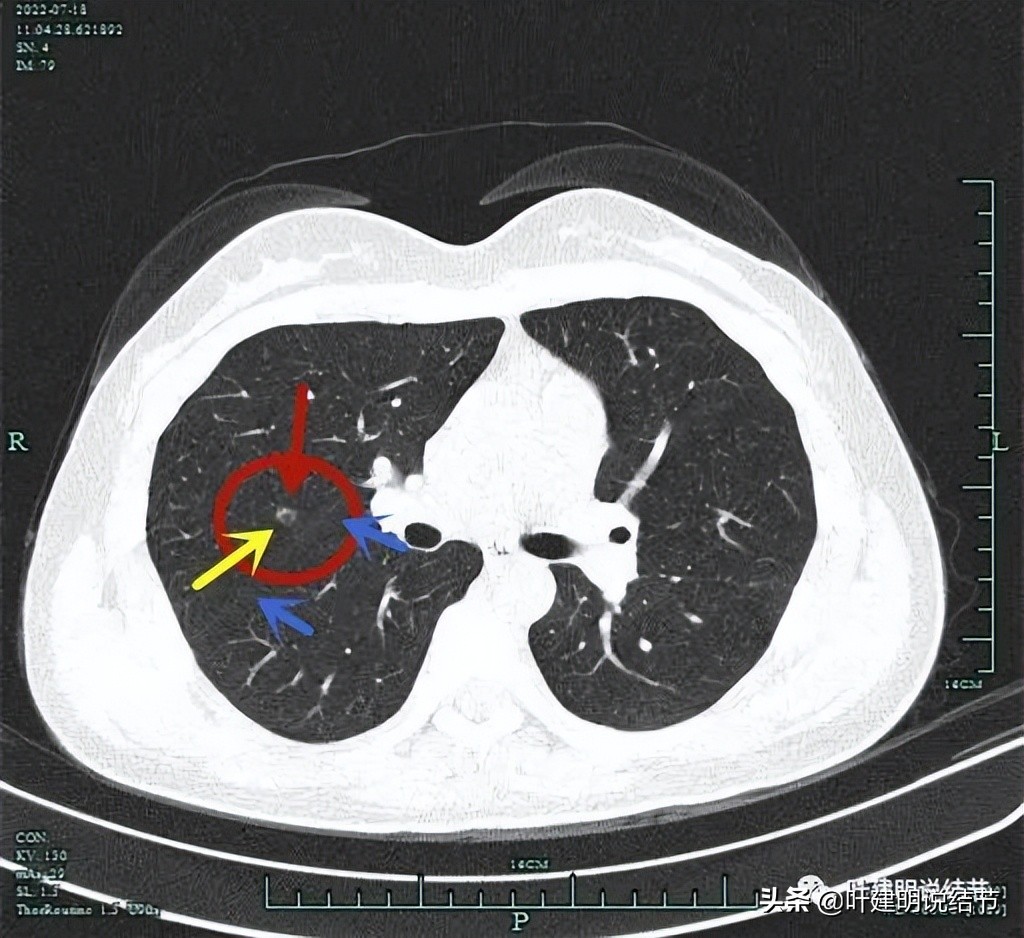

右上病灶虽然小,但密度感觉并不低,部分已经偏实性了,而且中间有小空泡征,应该要考虑恶性范围的,我判断大概率会已经是微浸润性腺癌了,至少是原位癌,但原位癌密度一般较这个要低一点。关键是位置确实挺尴尬,在右上叶邻近水平裂,与中叶交界的地方,距离肺门部大概仅约2厘米许,而且是在上叶凹进去的这个平面上,楔形切除的话,一是切割缝合器很难放到结节深面去,二是离肺门部血管近,又没有弧形的切割缝合器,容易伤到肺门部血管,许多医生可能会选择肺段切除以保证病灶能完整切除又不伤及肺门部结构。下面粉色虚线示结节到肺门血管的距离:

上图蓝色箭头示叶裂、红色示病灶轮廓与瘤肺边界清、黄色示中间有小空泡征,粉色箭头示结节与肺门部的距离仅不足2厘米,很难放置切割缝合器。